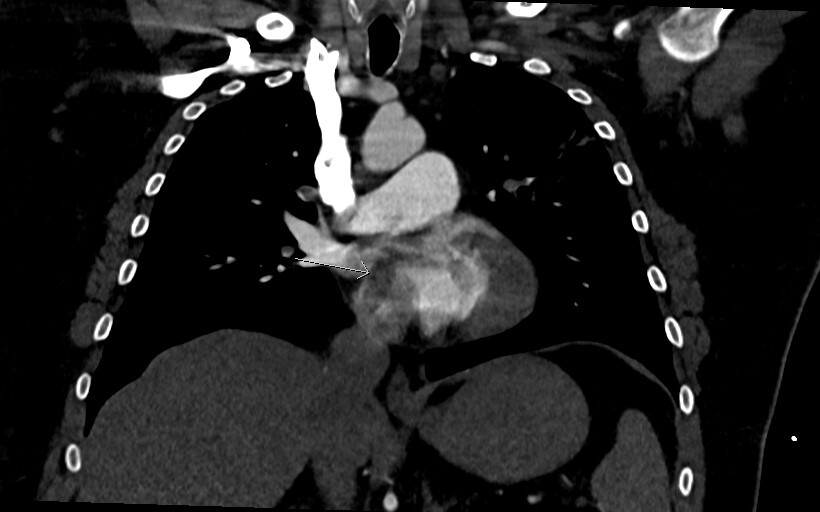

Figure 4 is a coronal image and shows the thrombus in transit again with a “boomerang” shape across the IAS (arrow heads).